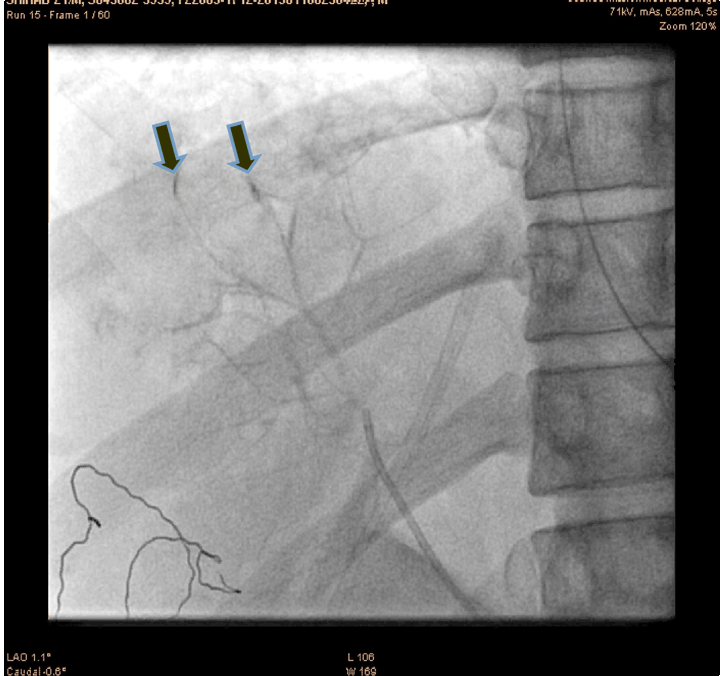

A 21-year-old male presented to the emergency department with alleged history of fall from height of about 10 feet three hours back. The patient was fully conscious and oriented with patent airway and normal breathing and ventilation. On examination, hypotensive (blood pressure 70/50 mmHg), tachycardia (110 bpm) and generalized abdominal tenderness were found. Focused assessment with sonography for trauma (FAST) was positive. So an emergency ultrasonography and contrast-enhanced computed tomography (CECT) scan of the abdomen were done which confirmed significant hemorrhage consistent with a grade III injury by the American Association for the Surgery of Trauma Organ Injury Scale. The patient was resuscitated and shifted to the operation theatre for an exploratory laparotomy, laceration of 4x2 cm with active hemorrhage were noted, the surgeon was not able control the hemorrhage successfully. So the patient was shifted to cath lab. An angiogram of superior mesenteric artery (SMA) showed bleeding from accessory hepatic artery (Figure 1). The diagnostic catheterization of accessory hepatic artery, followed by gel foam infusion to the accessory hepatic artery (Figure 2) and (Figure 3). Figure 4 shows the distal part of accessory hepatic artery occluded. Figure 5 shows occluded right artery following embolization. Repeat arteriography confirmed the occlusion of the vessel. The patient was then transferred to the ICU and transfused one unit of whole blood. He remained hemodynamically stable thereafter, without significant decrease in hematocrit. The patient gradually improved over the next several days and was discharged after two weeks. Follow-up CT scan one month after discharge showed a mild hematoma with no evidence of any infection or complication of the embolization procedure.

Figure 3: Injecting gel foam in to the bleeding accessory hepatic artery (arrow showing bleed site).